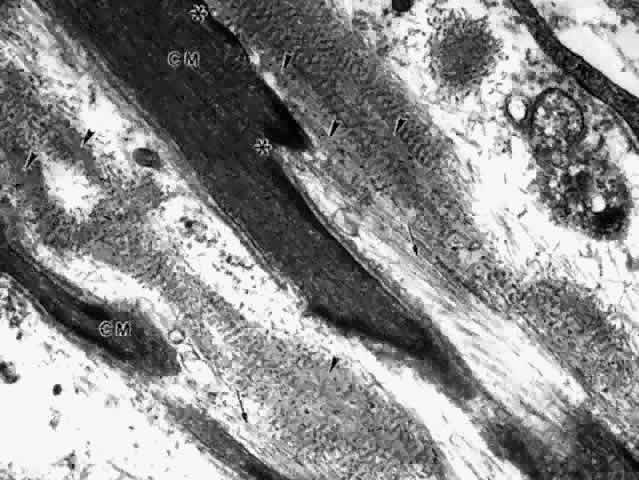

The ultrastructure of the ciliary muscle fibers resembles that of smooth muscle elsewhere, with a few interesting differences. The muscle bundles are surrounded by a sheath of flattened fibrocytes rather than primarily by collagen fibers (Fig. 37),46–48 showing that they belong to the multiunit family of smooth muscles instead of the syncytial family.49 Each fiber is covered by a continuous basement membrane and has many pinocytotic vesicles or caveolae on the plasmalemmal membrane. The fiber is filled with 60- to 70-nm myofibrils that show the usual attachment densities among them, as well as focally where they attach to the basement membranes (Fig. 38). These myofibrils are the intermediate filaments of the cell and contain the protein desmin, used to identify smooth or skeletal muscle cells by immunohistochemistry. A less specific protein, smooth muscle actin, is also present but characterizes myofibroblasts as well. Mitochondria and endoplasmic reticulum are more numerous and Golgi apparatus better developed than in most smooth muscle cells. Occasional desmosomes interconnect the cells but no gap junctions. Studies of muscle enzymes have suggested that there may be functional differences between the longitudinal muscle and the radial-circular muscle complex.50 The longitudinal muscle cells, particularly their anterior tips, are heavily fibrillar with fewer mitochondria than the other muscles and have enzyme characteristics somewhat like those of skeletal rapid twitch fibers. It is hypothesized that their multiunit structure might allow the muscle tips to react first in accommodation, stiffening them to counteract the posterior pull of the remaining muscle on the scleral spur.

Fig. 37. Inset. Thin fingers of fibrocyte cytoplasm (arrows) surround a bundle of ciliary muscle fibers. Main figure. Three muscle fibers (m) surrounded by processes of a fibrocyte (f). Thick basement membrane around each muscle fiber and several nerve terminals are visible. (X 33,800; Inset, X 8500)

Fig. 38. Elongated radial muscle fibers surrounded by basement membranes have large mitochondria, Golgi apparatus (g), and many central and peripheral densities (d). (X 21,400) Inset. The plentiful smooth muscle myofibrils in the cytoplasm attach to the densities in both central and peripheral locations (d). (X 70,000)

The ciliary muscle is richly innervated with large numbers of cholinergic nerve terminals. These show primarily the small agranular vesicles characteristic of cholinergic neuromuscular junctions51 (Fig. 39), consistent with the virtually complete inhibition of ciliary muscle contraction resulting from use of atropine. Most investigators have described three types of neuromuscular junctions in the ciliary muscle.46–48,51–53 The most common synaptic junction has an indirect muscle cell contact, with basement membrane intervening; direct contacts are less frequent (see Fig. 39).

Fig. 39. Dense and lighter muscle fibers (m) around an unmyelinated nerve fiber terminal that contains many mitochondria and small agranular synaptic vesicles (arrow), indicating that this is aneuromuscular parasympathetic junction. Indirect contacts with intervening basement membrane and one (asterisk) site of direct cell-to-cell contact are seen. (X 53,000)